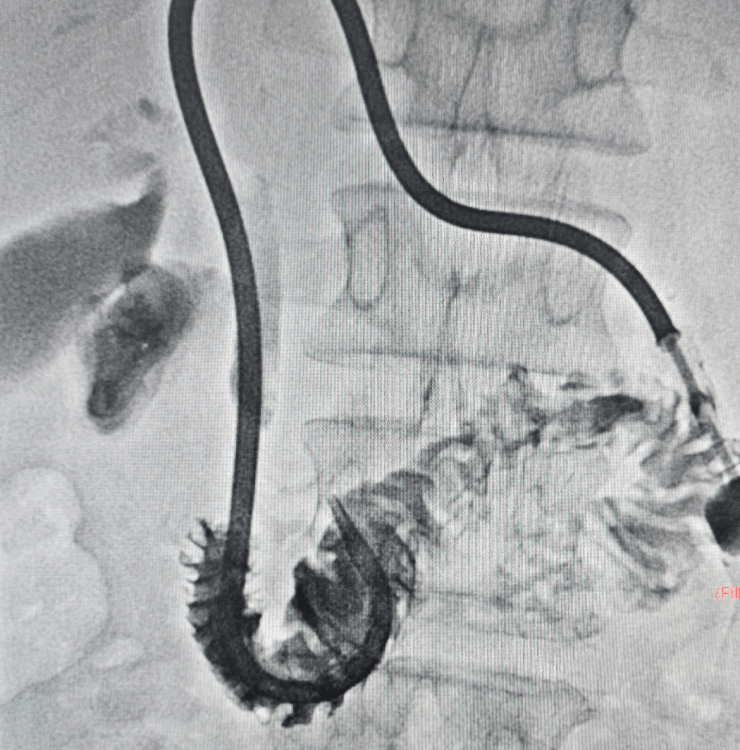

Percutaneous Transhepatic Biliary Drainage (PTBD) and biliary stenting are minimally invasive procedures that use imaging guidance to open blocked bile ducts and divert bile flow, helping reduce jaundice, itching, infection risk and improve overall condition.

PTBD and biliary stenting are performed under ultrasound and fluoroscopy (X‑ray) guidance, usually under local anesthesia with sedation.

- Needle access into a bile duct through the skin and liver using ultrasound and X‑ray guidance.

- Cholangiogram (bile duct contrast study) to identify the exact site and extent of blockage.

- Drainage catheter placement to temporarily drain bile outside or into the intestine (internal–external drainage).

- Definitive stenting across the blockage using plastic or metal stents to restore long‑term bile flow.